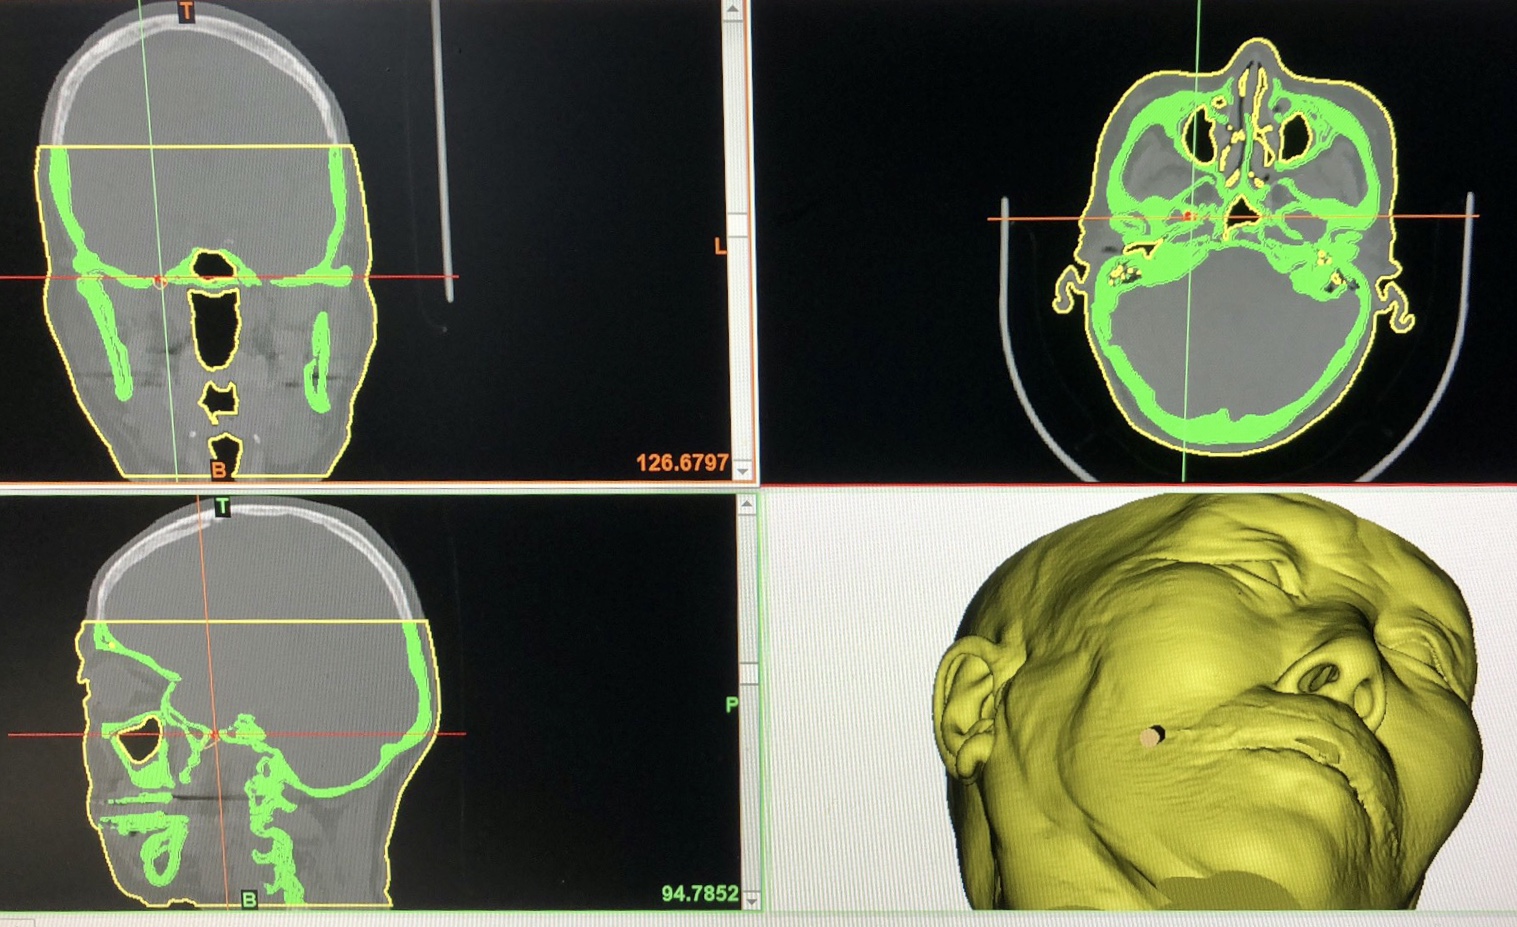

这就对手术团队提出了更高的技术要求,首先,需要通过颅脑CT扫描,在计算机中重建袁阿姨头面部三维模型,手术模拟穿刺点和穿刺过程,依据手术模拟结果在计算机中设计虚拟穿刺导引板,模拟在穿刺导引板引导下穿刺针位置、方向和深度,为手术提供关键信息。最后,我们利用3D打印技术打印出符合手术要求精度的实物导引板。

8月14日袁阿姨被推进导管室,术中3D重建后选择最优投照角度,在双C正侧位透视下,3D导引板引导穿刺针顺利植入卵圆孔内,进而置入球囊,充盈压迫3分钟后撤出,整个手术操作时长10分钟。术后袁阿姨颜面部疼痛即刻完全缓解,而创口仅仅是面部口角旁的一个小针眼,3天后袁阿姨顺利出院。